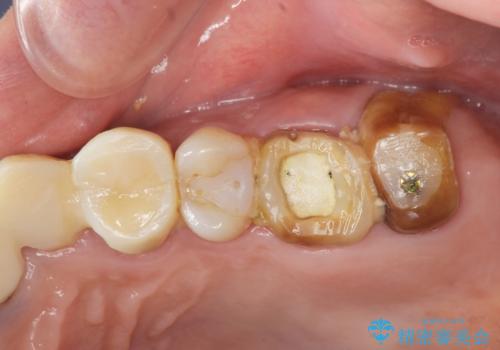

- 治療途中で前歯科医院に行かなくなってしまい、治療の続きを希望されて来院されました。

クラウンが装着されておらず、つぎはぎだらけの処置歯を、精度の高いセラミッククラウンを用いて歯ブラシのしやすい環境整備を行っていきます。